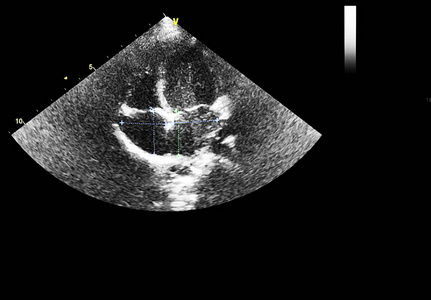

超声心动图(4腔视图)

心尖四腔心切面二维超声心动图